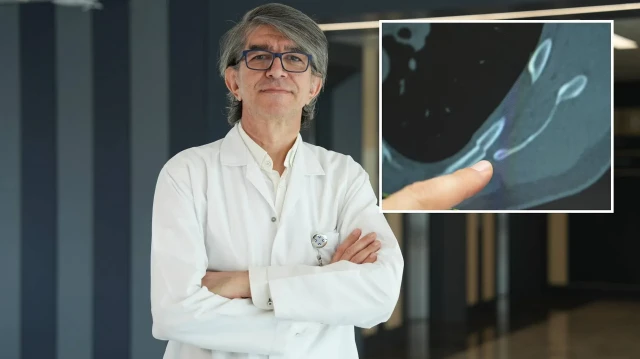

Ani başlayan ve geçmeyen göğüs ağrısı genç yaşlarda da ciddi kemik problemlerine işaret edebilir. Medipol Sağlık Grubu’ndan Göğüs Cerrahisi Uzmanı Prof. Dr. Güven Sadi Sunam, genç hastalarda öksürüğe bağlı kaburga kırıklarının görülme sıklığının arttığını ve bu durumun altta yatan önemli nedenleri olabileceğini belirtti.

Göğüs ağrısı deyince akla yaşlılar gelir ama son dönemde gençlerde de öksürük sonrası kaburga kırıkları artış gösteriyor. Medipol Bahçelievler Hastanesi’nden Göğüs Cerrahisi Uzmanı Prof. Dr. Güven Sadi Sunam, genç yaşta görülen kaburga kırıklarının ardındaki gizli tehlikeleri ve korunma yollarını paylaştı.